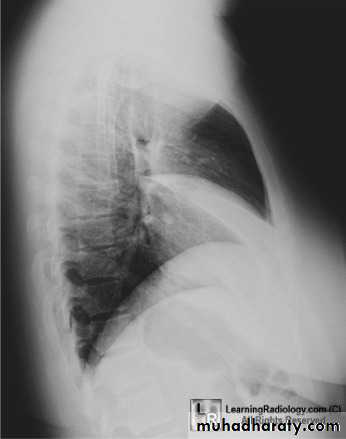

CXR of adult male ,PA and lateral views show:

Homogenus opacity in the left lower lobe triangular in shape

In the lateral view the density of the lower vertebrae is more than the upper vetebrae (abnormal)